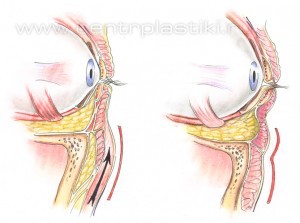

Рис. 2. Запавшие нижние веки после стандартной блефаропластики («трупный» вид) – произведено удаление внутриорбитального жира Современные методики блефаропластики подразумевают не удаление а, в большинстве случаев, сохранение или перераспределение внутриорбитального жира, подъем вверх опустившихся под действием силы тяжести тканей век, добавление взятой у того же пациента жировой ткани или введение в область век наполнителей, на основе гиалуроновой кислоты и лишь иногда – удаление жира. Что и позволяет в большинстве случаев вернуть векам молодость, объем и хороший внешний вид. Рис. 3

Рис. 6 Мышцу, аккуратно приподнимают и отделяют до края глазницы. Рис.7. Жировые «грыжи» опускаются вниз за край глазницы и фиксируются к надкостнице несколькими нитями, Рис. 8-9 таким образом, удается заполнить слезную и веко-щечную борозды Рис. 10.